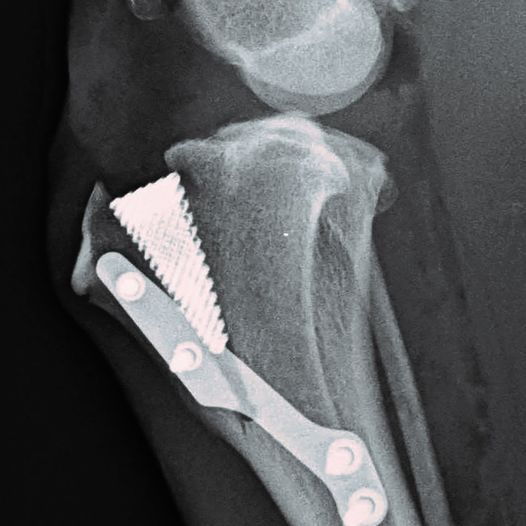

Cruciate surgery For Large Dogs – The TTA

Tibial Tuberosity Advancement

The TTA is one of the most popular treatments for Canine Cruciate Ligament Rupture.

The Tibial Tuberosity Advancement (TTA) surgery is one of the most commonly performed surgical procedures for the repair of Cranial Cruciate Ligament damage in dogs. It is the most common knee injury in the dog and it can occur at any age and in any breed, but most frequently occurs in middle aged, overweight, medium to large breed dogs.

What is the TTA Cruciate Ligament Surgery?

The TTA is widely considered the preferred way to repair cruciate ligament injuries in large dogs (over 20kg).

Hence, the TTA was developed and has rapidly become one of the most popular of the new tibial plateau levelling procedures. It is attractive to vets because it is simpler, faster, easier and more reliable than more complex procedures such as the TPLO.